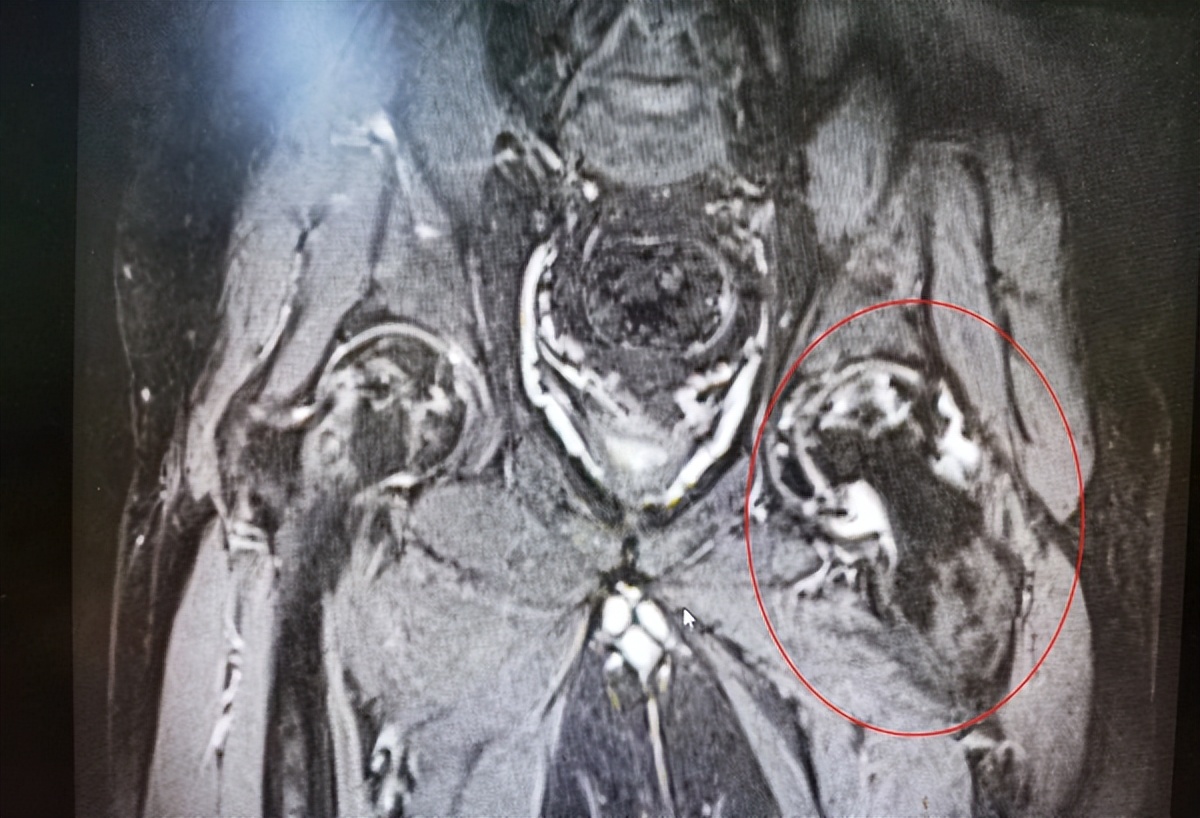

患者左侧股骨头坏死塌陷。通讯员陈梦圆 周丽 摄

6月底,小刘来到武汉市第四医院就诊。在该院创伤与关节二病区,接诊医生程可可发现小刘双侧股骨头均有坏死,尤其是左侧坏死严重,需要进行关节置换。令医护人员感到诧异的是,即便身体已频频报警,小刘仍未改掉“以饮料代水”的习惯,入院时尿酸高达700umol/L。经过医护人员反复劝说,小刘才暂时戒掉饮料,尿酸迅速恢复正常值。上周,医生顺利为小刘进行左侧髋关节置换。